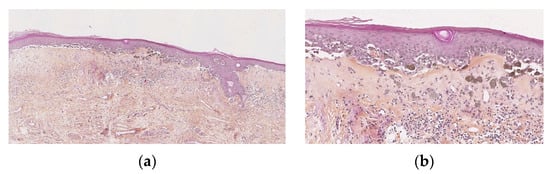

Vulval LS in children shows the same characteristics as described in adults, i.e., vacuolar interface dermatitis with an atrophic epidermis, band-like dermal fibrosis and lymphocytic infiltrate. The most constant signs, found in more than 90%, are hyperkeratosis, low lymphocytic exocytosis, vacuolization of the basal keratinocytes and dermal superficial sclerosis with hyalinized collagen. In 40 to 90% of the cases, epidermal atrophy, basal apoptotic keratinocytes, a band-like lymphocytic infiltrate (moderate to severe), interstitial infiltrate, ectatic vessels, and melanophages may be seen (Figure 1a). Surprisingly, basement membrane thickening and hyalinized vessels are rare (8 and 23%, respectively), while it is very common in adult vulval LS, perhaps being a long-term effect. One finding, not well documented in the literature, that could be a peculiarity of paediatric vulval LS is periappendageal and, in particular, perifollicular dermatitis with lymphocytic exocytosis, vacuolization of keratinocytes, apoptotic keratinocytes at the hair follicle, sometimes with follicular acanthosis and basal membrane thickening. However, there is also lymphocytic syringotropism, acrosyringeal acanthosis, and the influx of neutrophils (neutrophilic syringotropism) into the sweat gland epithelium and basal membrane thickening (Figure 1a–c) [7,10].

Figure 1.

Lichen sclerosus. (a) Typical lichen sclerosus: hyperorthokeratosis, epithelial atrophy, dermal superficial sclerosis containing melanophages, band-like lymphocytic infiltrate under the sclerosis. (b) Perifollicular lichen sclerosis: superficial sclerosis visible only around the ostium of a follicule and with underlying lymphocytic infiltrate. (c) Syringitis in lichen sclerosus: acrosyringeal acanthosis, and the influx of neutrophils) into the sweat gland epithelium and basal membrane thickening.

Statistically significant differences have been noted for some characteristics between infancy and the teenage years. Lymphocytic exocytosis of the epidermis is more important, and melanophages in the dermis and hyalinized sclerotic vessels are present more frequently in biopsies after puberty than those taken from girls under the age of 12, perhaps because of the longer duration of the inflammation [10].